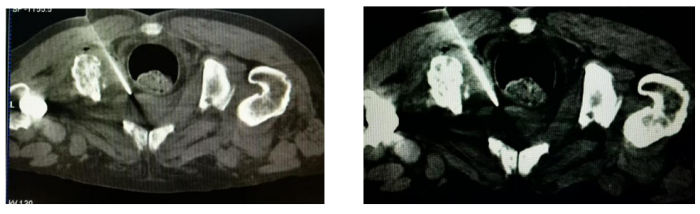

全面评估之后,李岳勇主任带领团队决定充分利用科室CT模拟定位机,为李爷爷实施肿瘤科首例CT引导下前列腺肿物穿刺活检术。通过高分辨率CT影像可清晰地勾勒出前列腺内微小病灶的精确位置。在李岳勇主任的指导下,苏天海医生通过影像的精准导航,将细针稳稳地送入目标区域,成功获取了关键的组织样本。整个手术过程顺利,患者全程无明显不适感,术后生命体征平稳。

患者俯卧位,穿刺活检针经过臀部到达前列腺部位